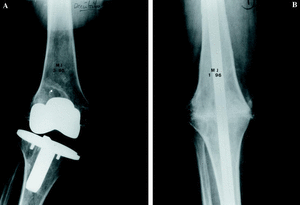

Entre diciembre de 1991 y marzo de 2000 se realizaron 21 artrodesis de rodilla mediante enclavado endomedular. El estudio está basado en el análisis retrospectivo de estos procedimientos y su evolución. De los 20 pacientes, en un caso se realizó artrodesis en ambas rodillas aunque no coincidieron en el tiempo; 15 fueron mujeres. La edad media, en el momento de la cirugía, fue de 67,8 años (mínimo 17 y máximo 82 años). La causa de la artrodesis fue el fracaso de la artroplastia en 18 casos, un osteosarcoma en metáfisis femoral distal en un varón de 17 años, una gonartrosis severa en una paciente con obesidad mórbida y artroplastia de la rodilla contralateral (Fig. 1) y, por último, una gonartrosis en un miembro afecto de poliomielitis.

Figura 1. Paciente con obesidad mórbida y artroplastia de rodilla contralateral. A: Radiografía preoperatoria. B: Radiografía a los 3 años de la cirugía, consolidación.